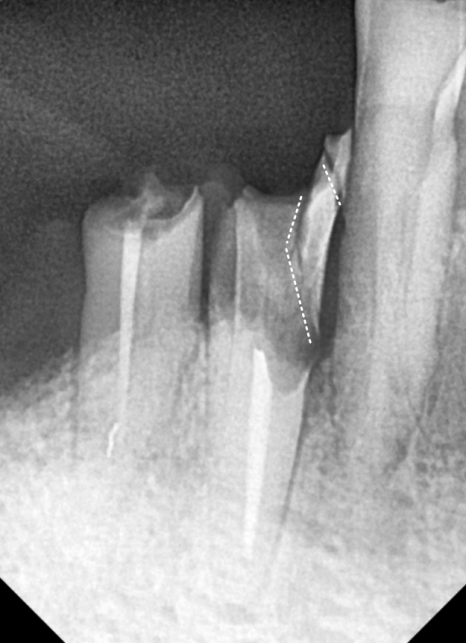

맨 끝 치아(#47) 역시 뿌리 끝에

고름주머니가 크게 잡혀 있었죠.

결국, 남아있는 뿌리 3개를 발치하고

튼튼한 임플란트 3개를 식립하는 것으로

치료 방향을 잡았습니다.